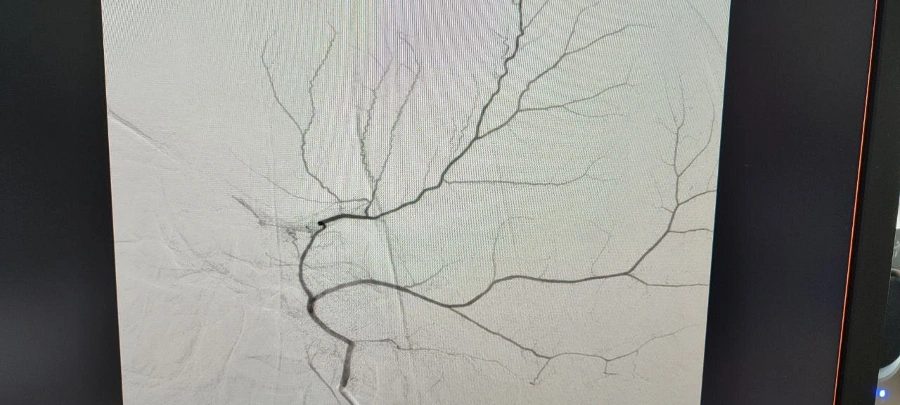

«После детального обследования врачом-нейрохирургом-эндоваскулярным хирургом Александром Юрьевичем Майоровым было предложено применить новую тактику. Операционной бригадой, в которую также вошли заведующий отделением РХМДиЛ, эндоваскулярный хирург Струбалин А.В., анестезиологи заведующий ОАР № 1 Савельев Ю.А. и врач-анестезиолог-реаниматолог Фокин С.А., медсестра-анестезист Благова А.М., операционная сестра Креккер Н.В., операционная санитарка Тюрикова Е.Н. успешно выполнила эндоваскулярную эмболизацию средней оболочечной артерии слева микрочастицами», - сообщили в БГКБ.

Медики поясняют, что эта передовая технология позволяет избежать сложного и травматичного открытого вмешательства на черепе, знаменуя собой новый этап в нейрохирургии региона. Суть новой эндоваскулярной методики заключается в прицельной внутрисосудистой окклюзии (закупорке) этой артерии, что прекращает питание капсулы гематомы и способствует её постепенному регрессу (рассасыванию), не влияя на кровоснабжение головного мозга. Данный подход радикально снижает риски осложнений и повторных гематом.